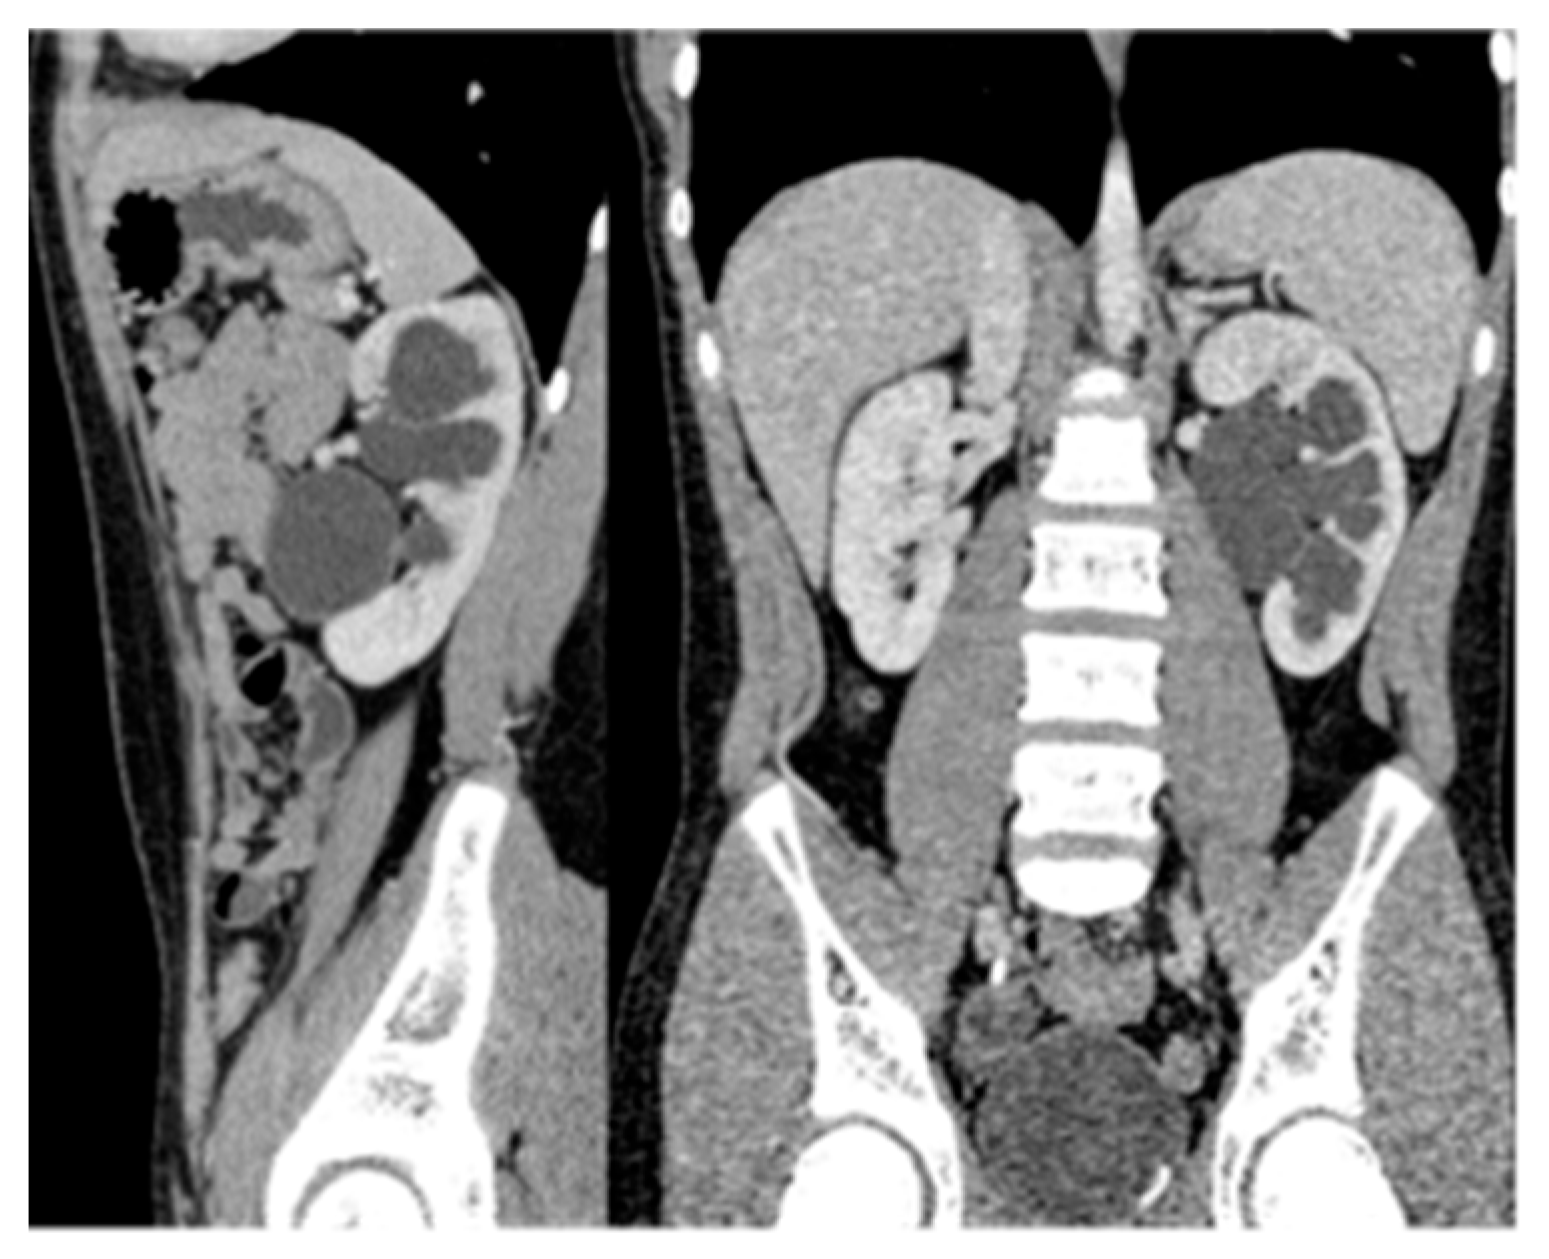

22. Renal Vascular Disease

Doppler US can be used to detect renal artery stenosis, but its sensitivity is limited [80]. MRI and CT angiography are more sensitive than US and can provide high-resolution images of the renal artery. However, they do not visualize distal branch artery lesions. Conventional angiography remains necessary to evaluate renal artery stenosis if it is clinically suspected (Figure 24) [80,81].

Figure 24. Angiography demonstrating focal stenosis (indicated by the arrows) in the segmental artery supplying the midportion of the right kidney in a 12-year-old male.

Medicina 61 00696 g024